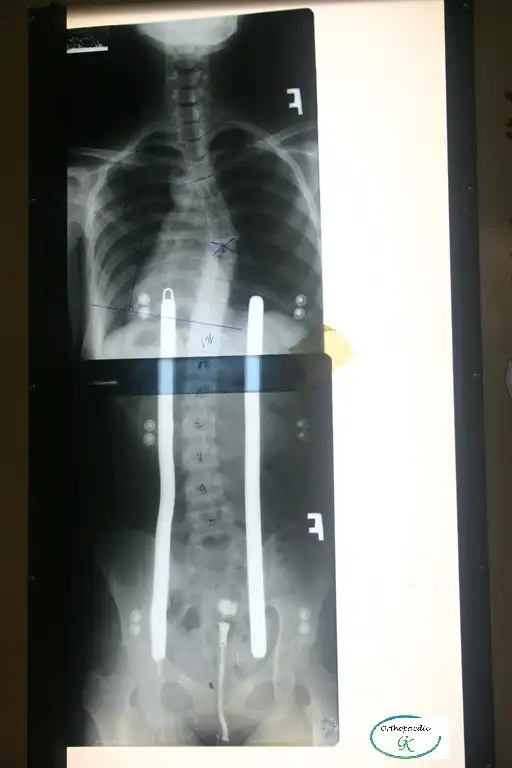

Điều trị vẹo cột sống

Có nhiều nguyên nhân khác nhau dẫn đến vẹo cột sống, bao gồm di chứng của bại liệt, bại não, tật nứt đốt sống, dị tật đốt sống và chấn thương hệ thần kinh-cơ-xương, nhưng trong phần lớn các trường hợp, không xác định được nguyên nhân cụ thể. Trường hợp này được gọi là vẹo cột sống vô căn (nghĩa là không rõ nguyên nhân).

Vẹo cột sống vô căn (Idiopatic Scoliosis): là tình trạng cột sống bị cong, vẹo mà không rõ nguyên nhân Đây là dạng thường gặp nhất trong các loại vẹo cột sống có cấu trúc cố định (tức là cột sống cong thật, không phải do tư thế). Bệnh thường bắt đầu ở trẻ em hoặc thanh thiếu niên và có thể nặng dần lên cho đến khi cơ thể ngừng phát triển xương (khoảng sau tuổi dậy thì). (Stagnara, 1988.)

Việc đeo Áo chỉnh hình (orthosis) thường có thể điều trị vẹo cột sống, tuy nhiên nếu góc cong của cột sống vượt quá 45º thì sẽ rất khó điều trị bằng phương pháp này. (Thomas M. Gavin và cộng sự, 2001)

Điều trị bằng nẹp chỉnh hình được khuyến nghị cho những bệnh nhân chưa trưởng thành về mặt xương khớp và có độ cong tiến triển từ 25º đến 45º (theo góc Cobb), trong khi phẫu thuật cố định cột sống được chỉ định cho các trường hợp có độ cong vượt quá 45º. (Thomas M. Gavin và cộng sự, 2001)